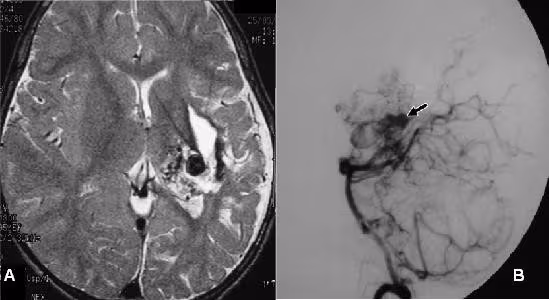

Việc chẩn đoán bệnh dị dạng động tĩnh mạch dựa vào các triệu chứng lâm sàng và các kĩ thuật thăm dò hình ảnh, bao gồm một hoặc nhiều phương pháp sau:

– Siêu âm Doppler mạch máu

– Chụp cắt lớp vi tính mạch máu (CTA)

– Chụp cộng hưởng từ mạch máu (MRA)

– Chụp mạch số hóa xóa nền (DSA)